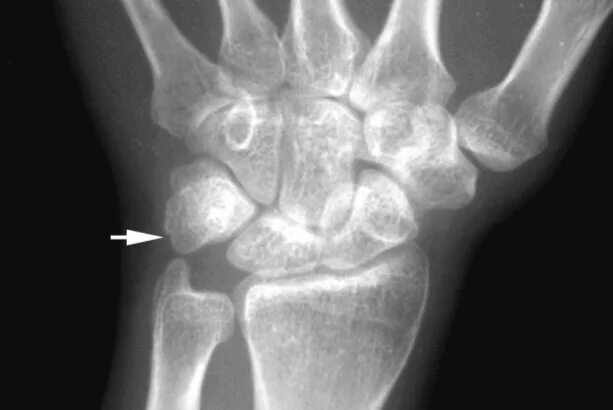

Перелом лучезапястного сустава мкб 10